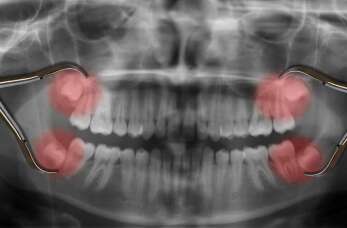

Usunięcie zęba mądrości to zabieg, który może wywołać niepokój u wielu pacjentów. Jednak wiedza na temat tego, czego można się spodziewać przed, w trakcie i po, może znacznie zmniejszyć stres...